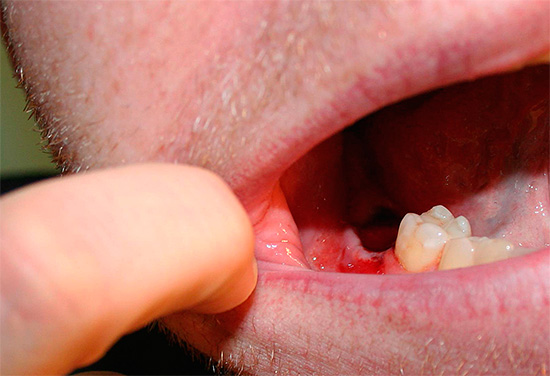

Alveolite

Alveolite, ou, caso contrário, inflamação das paredes do buraco após a extração dentária, pode ocorrer por várias razões. Listamos alguns deles:

- Cirurgia traumática.

- Empurrar profundamente o poço do instrumento com pedaços de tecido cariado infectado em um dente ou placa dentária removidos.

- Violação da integridade dos ossos dos alvéolos, deixando bordas agudas e feridas na gengiva.

- Sangramento prolongado do buraco.

- A ruptura de um coágulo sanguíneo ou a sua ausência no buraco.

- Violação do regime de tratamento de feridas no pós-operatório pelo próprio paciente.

Geralmente, sob a influência de um ou mais fatores provocadores, a alveolite se desenvolve 1-3 dias após a extração do dente com uma clínica com agravamento do estado geral, mal-estar, febre, dores agudas nas gengivas, mastigação prejudicada ao lado da remoção e aparecimento de mau hálito.